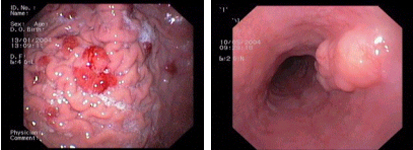

imagen2

Sarcoma de Kaposi en el estómago - Tumor submucoso esofágico